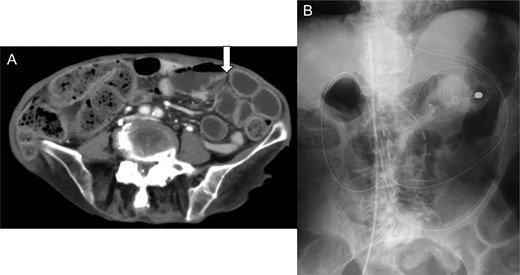

We reviewed the abdominal CT on admission, which revealed a deficit in the urinary bladder wall, with fluid collection around it (Fig. 3). The perforation of the urinary bladder was present on admission, and that of the peritoneum occurred on the following day. Previous magnetic resonance imaging revealed no diverticulum of the urinary bladder or any organic failure.

Review of the enhanced abdominal computed tomography on admission after the operation revealed (A) fluid collection in the posterior space of the urinary bladder (black arrow) and (B and C) deficit in the urinary bladder wall and suspected perforation (white arrow).